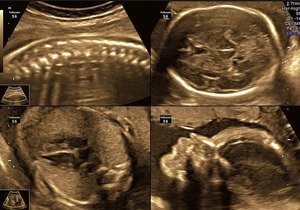

TIFFA SCAN- TARGETED IMAGING FOR FETAL ANOMALIES

TIFFA (Targeted Imaging for Fetal Anomalies), also known as a detailed anomaly scan, is a specialised ultrasound to evaluate the fetus comprehensively in complete detail. This targeted scan is crucial for detecting structural abnormalities in the developing fetus. It is performed only by experts. It can be called the most important scan in pregnancy.

This is a very detailed scan where the entire fetus is checked thoroughly in detail from head to foot. to summarize very briefly all that is checked includes- the fetal head and brain, fetal face including the eyes, the nose including the nasal bone, the lips, the fetal neck, the fetal chest including details of the fetal heart, the fetal lungs, the diaphragm that is the partition between the chest and abdomen, the abdominal organs including the stomach, kidneys and bladder, the umbilical cord, the fetal limbs-that is the hands and legs. The fetal gender is not revealed during the scan in accordance with the PNDT guidelines.

TIFFA- fetal face- profile